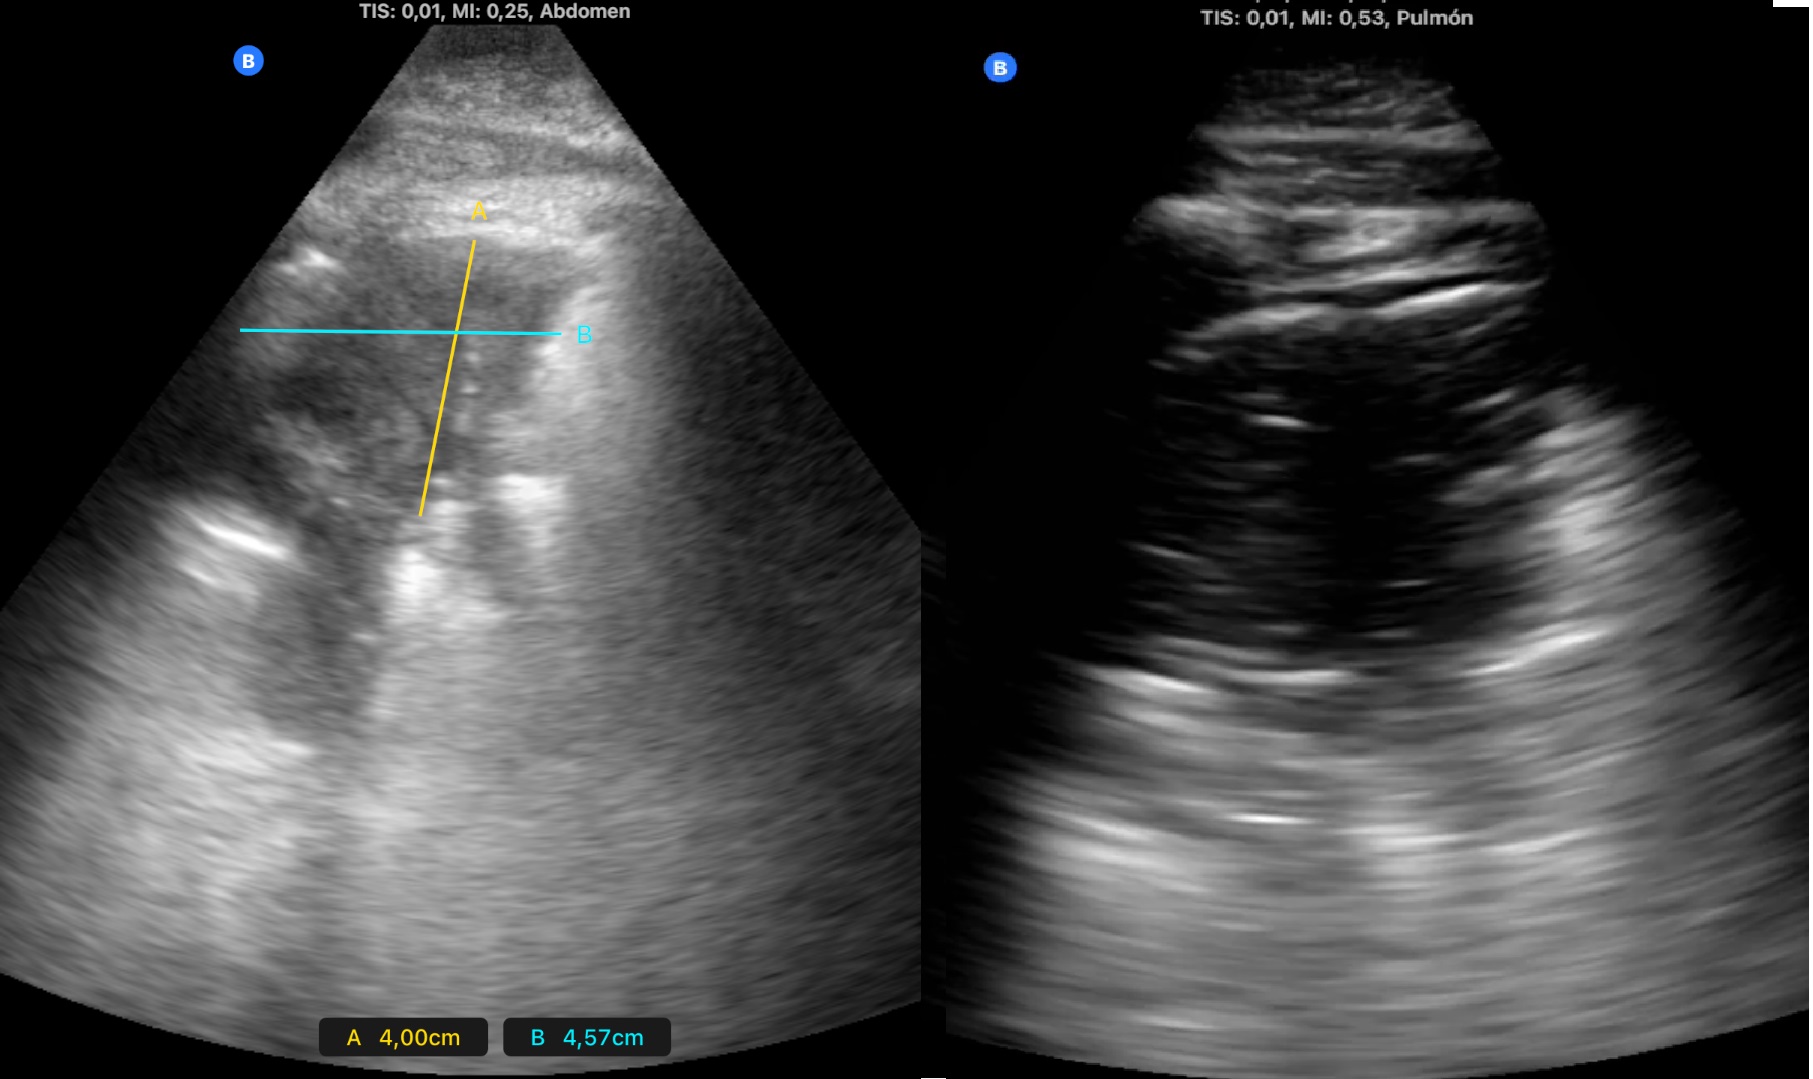

2. Consolidación de mayor tamaño (figura 2), con zonas de pulmón blanco y líneas B confluentes adyacentes a la misma (figura 3), en zona anterior y lateral derechas. Se vuelve a auscultar apreciando sólo leve disminución de murmullo vesicular en la zona.

2. Radiografía de tórax con consolidación en lóbulo medio tras los hallazgos ecográficos (figura 4).